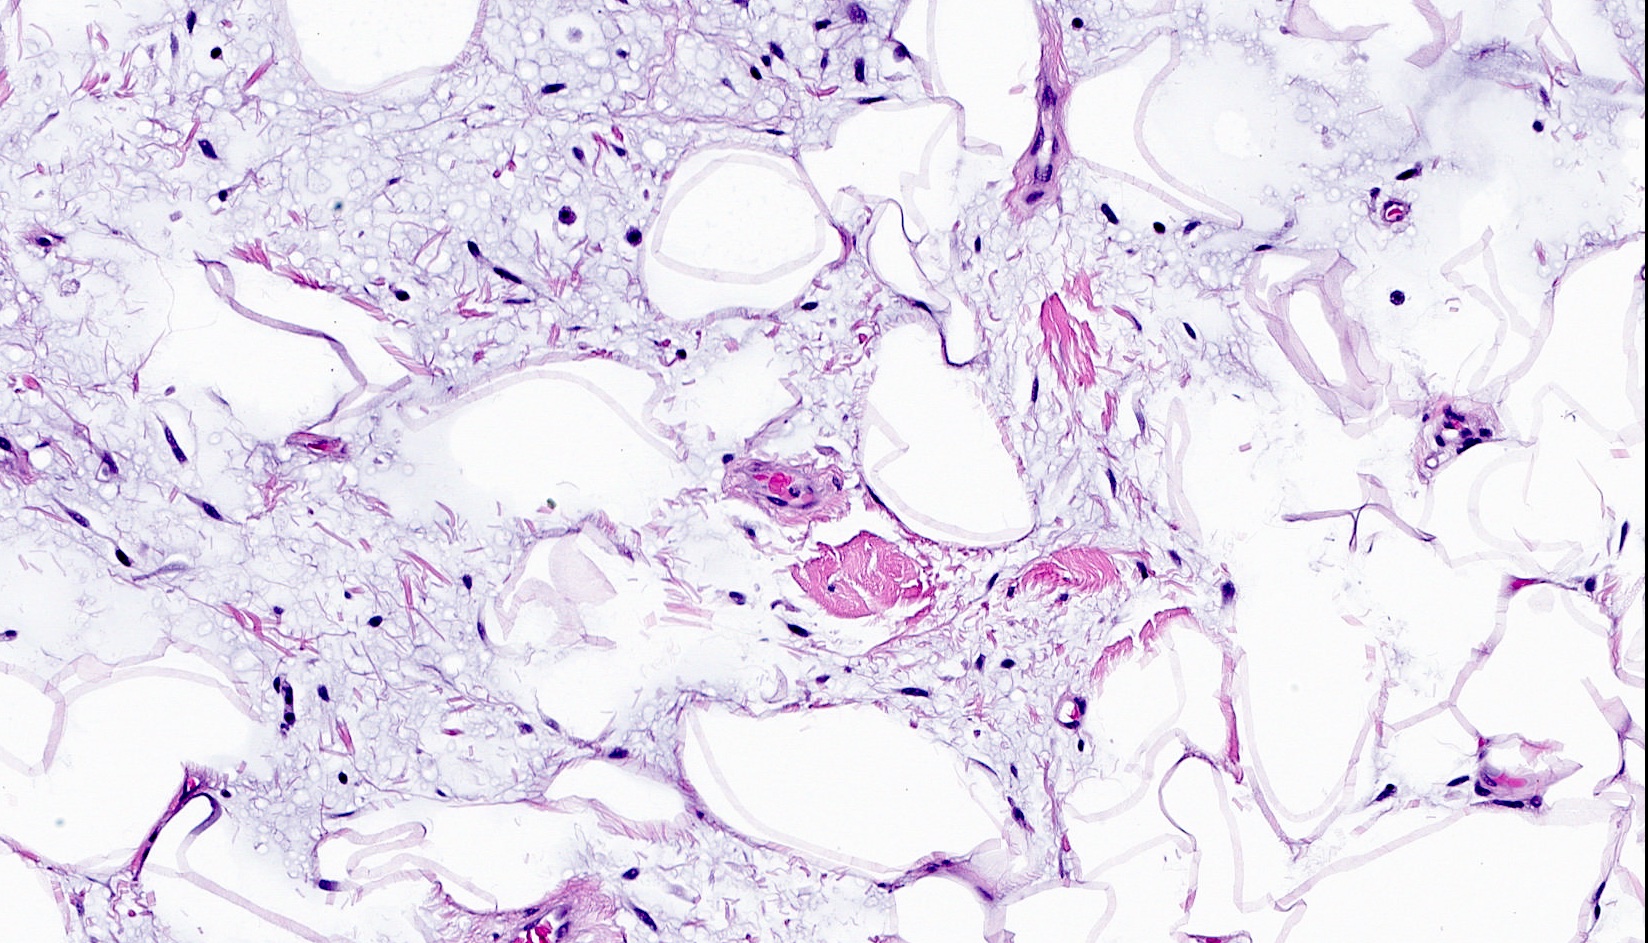

Microscopic (histologic) images

- Bland, uniform, short to elongated spindle cells arranged as short haphazard intersecting fascicles admixed with bands of hyalinized, brightly eosinophilic collagen and variable amounts of fat

- Focal myxoid stromal changes common

- Myxoid: stellate and spindle cells in abundant myxoid stroma (Histol Histopathol 2016;31:1)